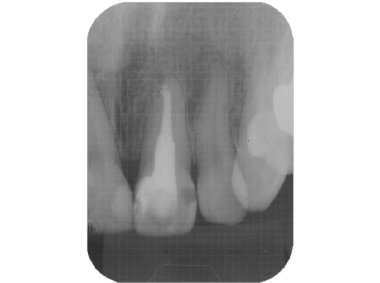

緊密な根管充塡

清潔な無菌的な根管の清掃が終了したら、緊密に根管充塡を行います。レントゲンで白く写る部分です。

根管治療の最後の処置です。根管の解剖学的な形態、彎曲度合い等によって数種類の根管充塡システムを当院では使い分けています。

- 根の治療は終わったと言われたそうですが、、、、